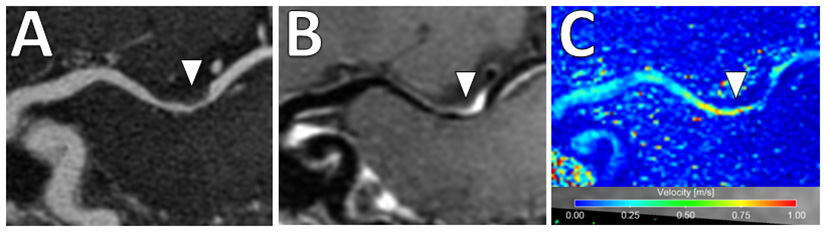

In addition, there is increased interest in characterizing velocity using 4D Flow MRI. This is an advanced phase-contrast MRI technique which allows non-invasive quantifications of blood flow to characterize the hemodynamic impact of intracranial atherosclerosis and identify hemodynamic biomarkers (96) (Figure 9). While studies to date share limitations including long scan duration, low spatial/temporal resolutions and associated tradeoffs (97), this is a promising emerging technique.

Figure 9

4D Flow MRI of intracranial atherosclerosis. (A) TOF MRA image demonstrates a focal area of middle cerebral artery narrowing (arrowhead) with (B) post-contrast T1-weighted VW-MRI showing a corresponding eccentric, enhancing atherosclerotic plaque (arrowhead). (C) On 4D Flow MRI, increased velocities are seen in the area of greatest narrowing (arrowhead).